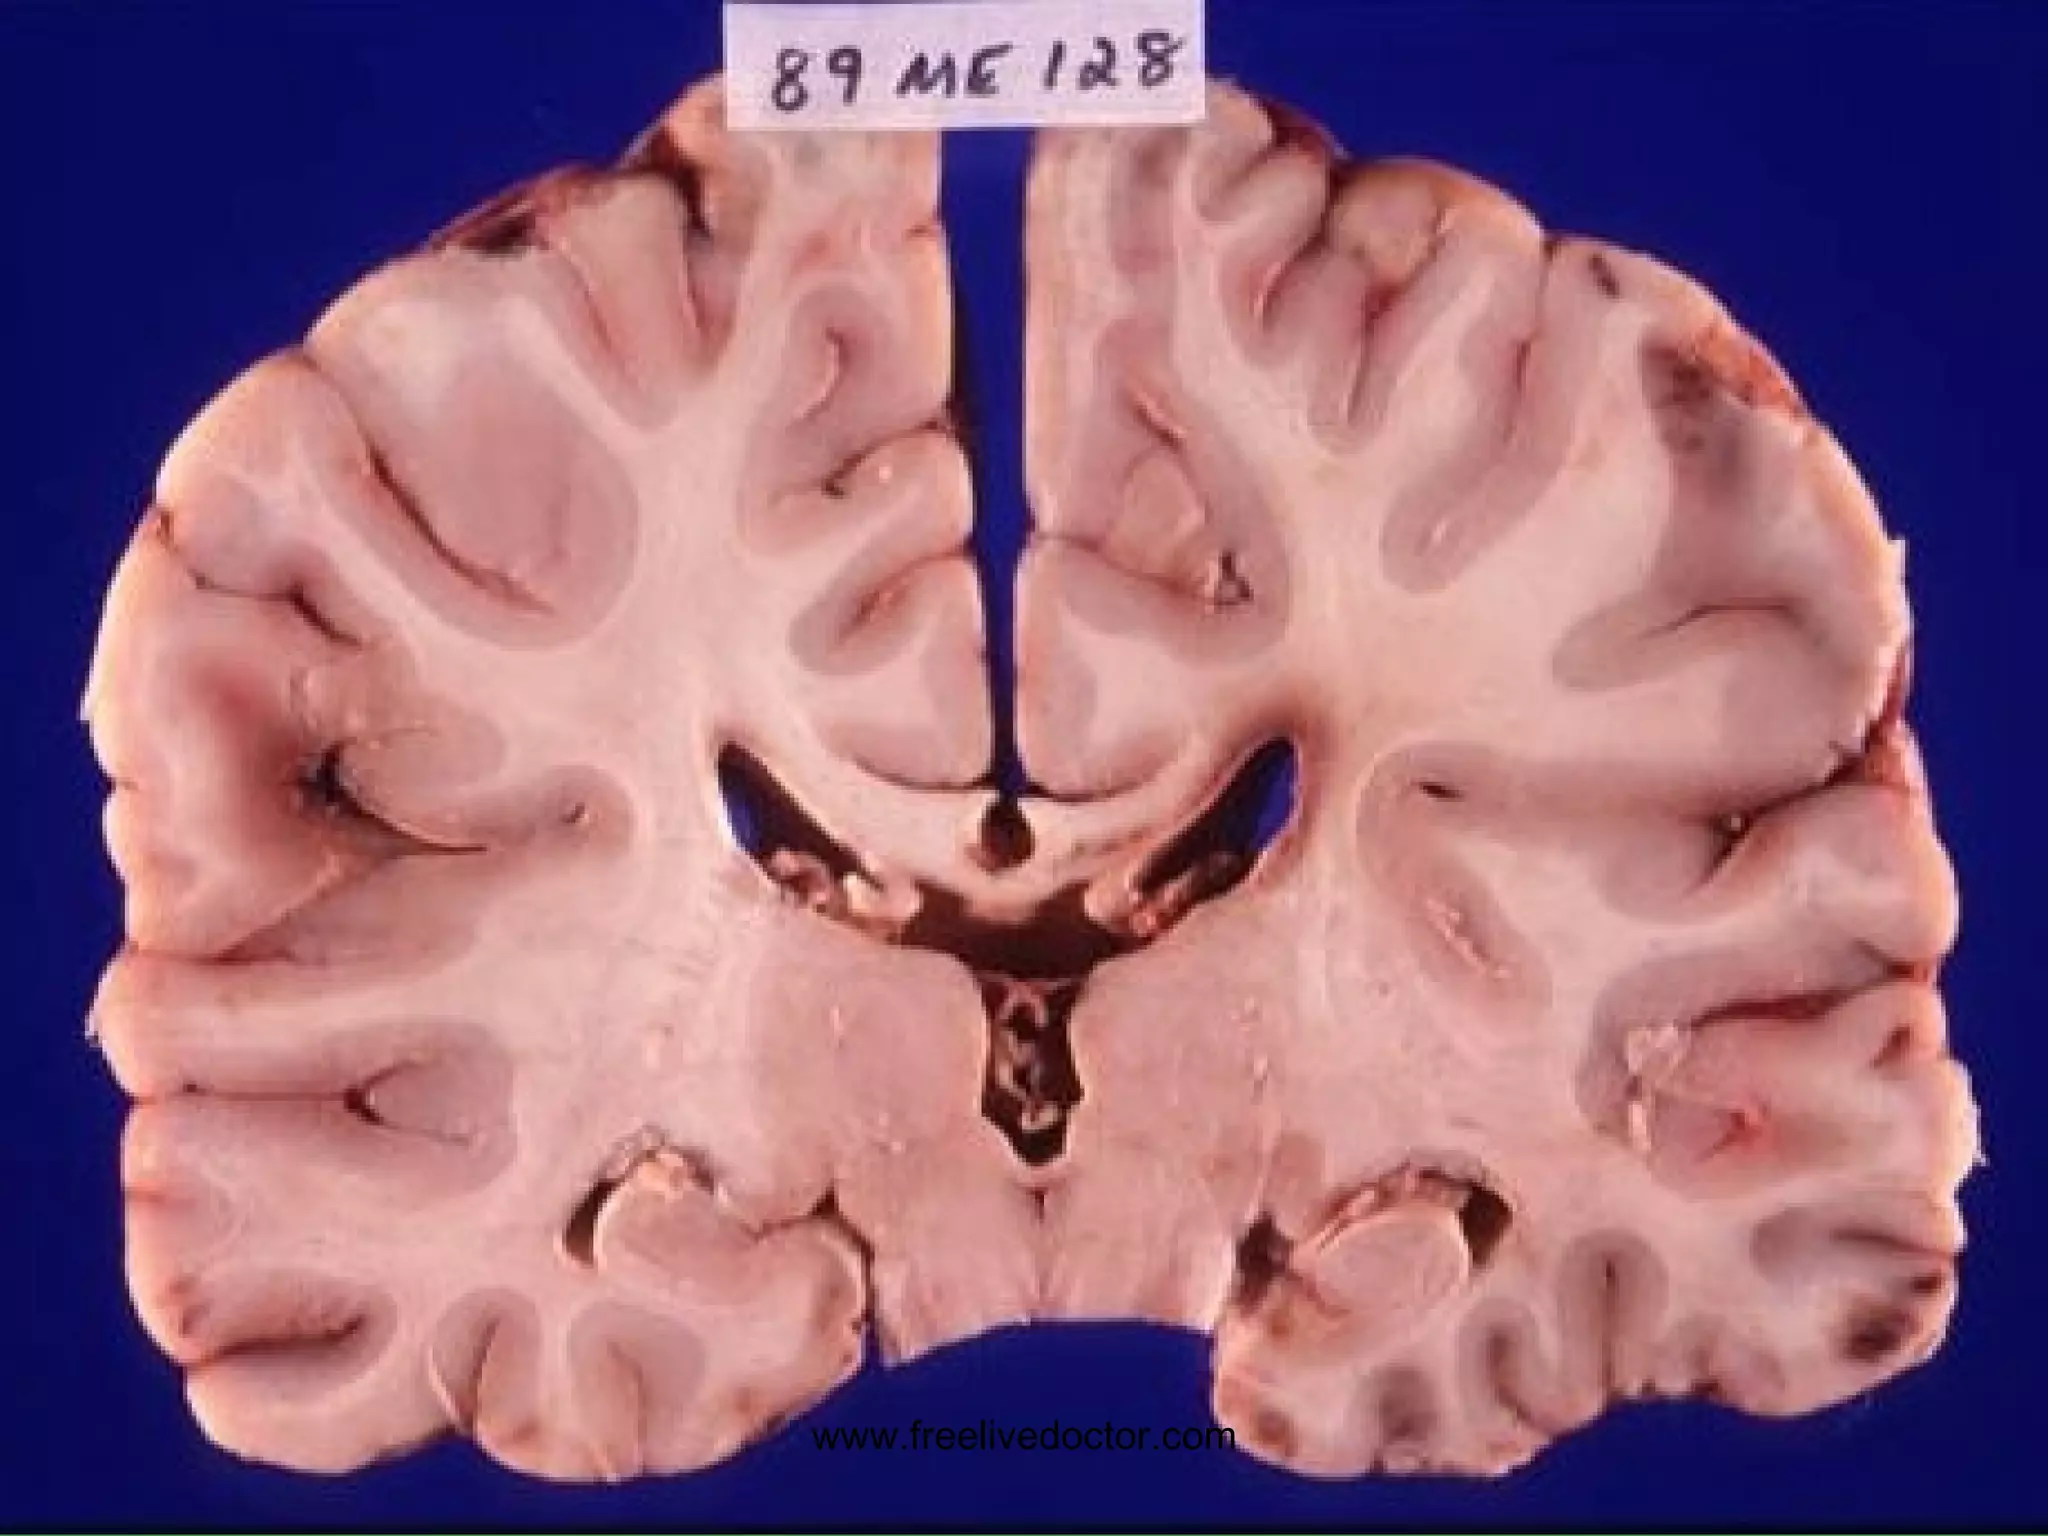

HYDROCEPHALUS www.freelivedoctor.com

HYDROCEPHALUS Impaired RESORPTION Increased PRODUCTION OBSTRUCTION COMMUNICATING (entire) NON-COMMUNICATING (part) HIGH Pressure NORMAL Pressure www.freelivedoctor.com

• #28 Basic pathophysiologic concepts about hydrocephalus which is defined as any major deviation from the normal physiology of CSF

• #29 Hydrocephalus on CT

• #30 Hydrocephalus on MRI

• #31 Hydrocephalus also showing cerebral edema, CT or MRI? Ans: CT Why? Ans: Bone is always very dense on CT, and water is always intense on T2 weighted MRI

• #32 Hydrocephalus, dilated ventricles